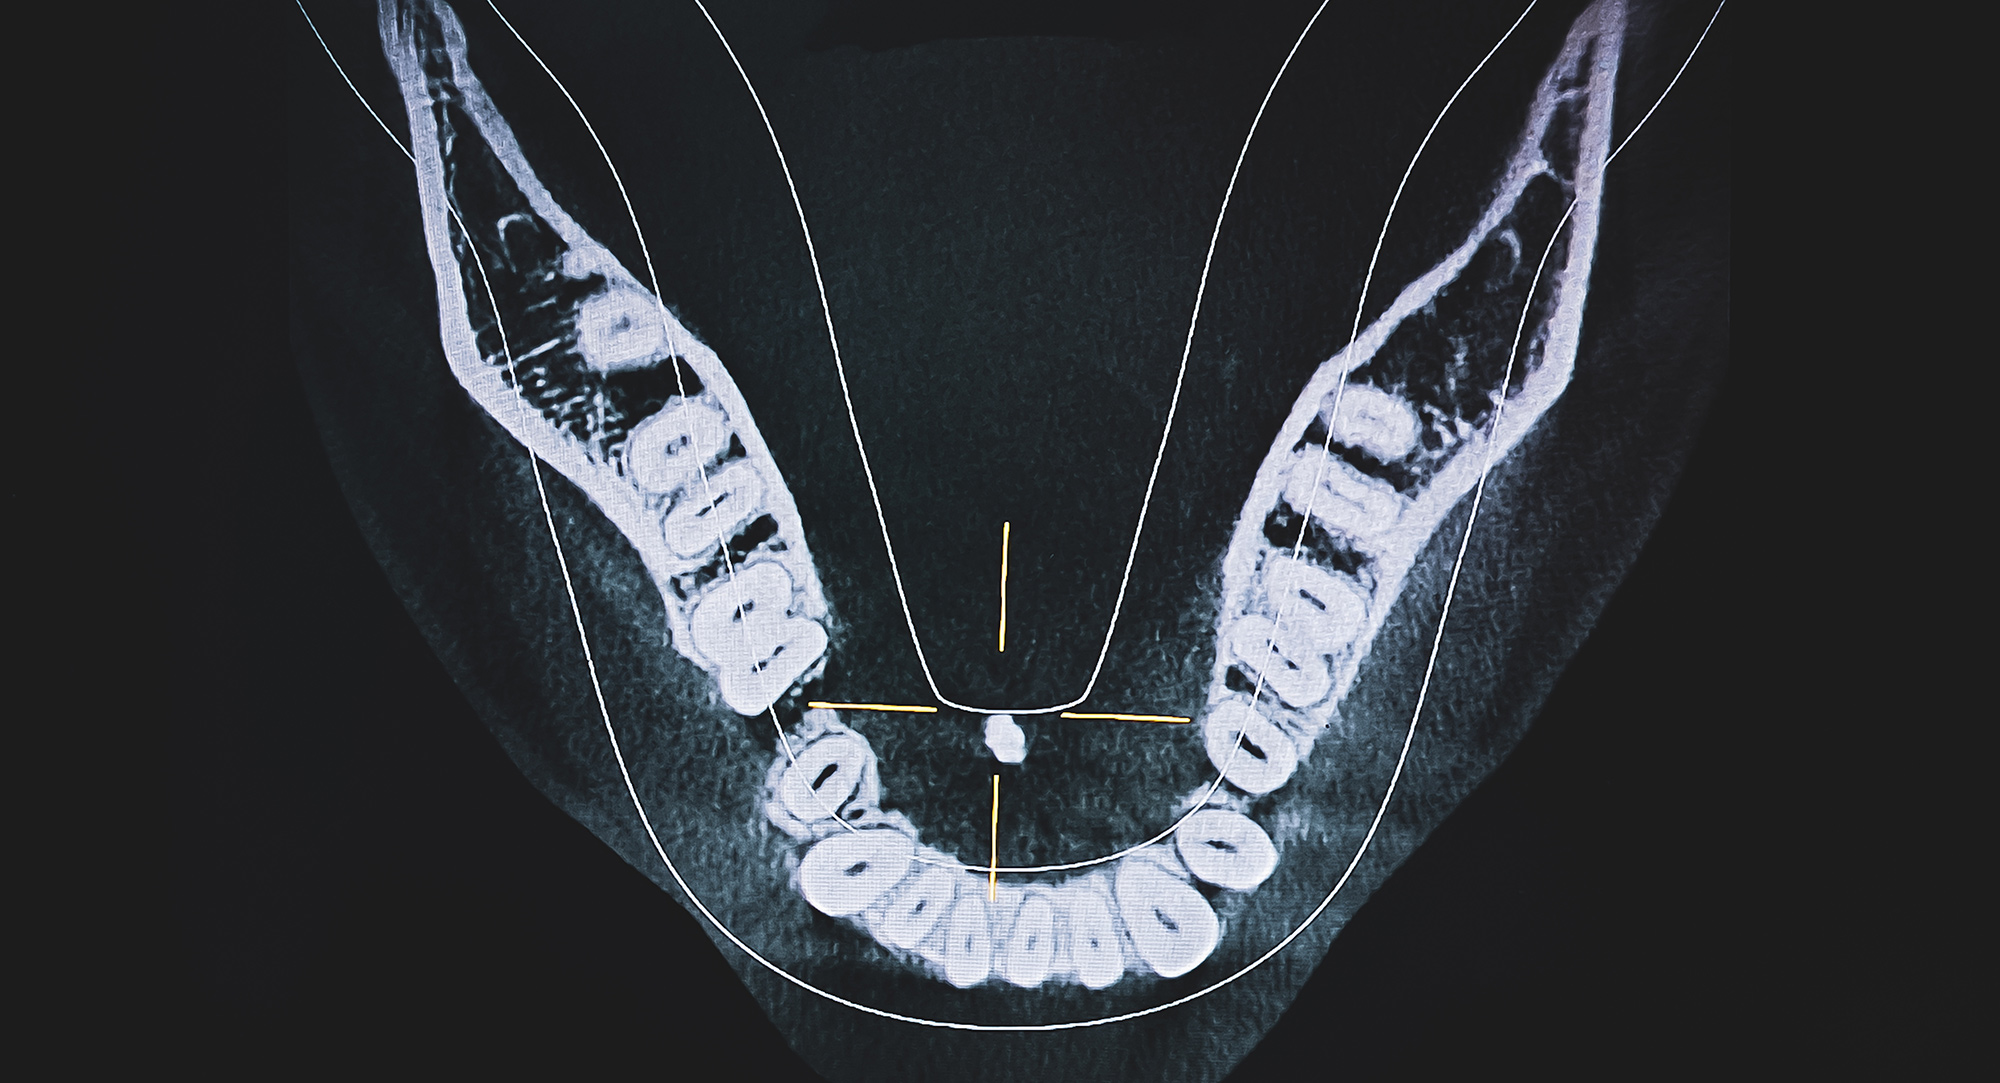

At Head2Neck, diagnosis is carried out by Consultant Surgeon Mr Konstantinos Karavidas, who specialises in salivary gland conditions. Assessment begins with a medical history and examination, followed by imaging such as ultrasound, MRI, or CT to confirm any salivary duct obstruction.

In some cases, sialendoscopy is used, allowing direct visualisation of the ducts and accurate identification of stones. This thorough approach ensures treatment is precise and effective.